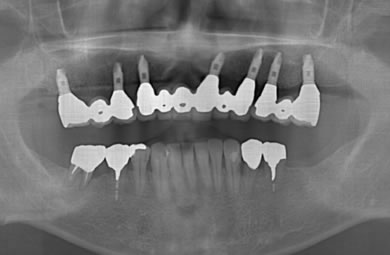

| 治療方針 | 骨再生療法にて上顎の骨を増やしインプラント治療にて審美的・機能的回復を行う。 | ||||||||||||||||||||||||||||||||

| 治療内容 | インプラント7本(ソケットリフト)、ハイブリッドセラミック12本 | ||||||||||||||||||||||||||||||||

| 総治療費 | 3,207,924円 | ||||||||||||||||||||||||||||||||

| 治療期間 | 1年6ヶ月 |